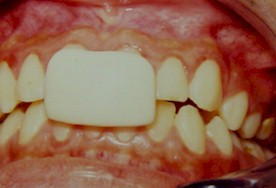

Se fijó un electrodo de superficie por

cada músculo a registrar uniendo los cables de registro del Electromiógrafo con

su correspondiente ubicación (Foto 1 y 2). Se realizó el test de ruido para

Foto

1.- Colocación de electrodos de registro a nivel del músculo temporal

Foto 1.- Colocación de electrodos de registro a nivel del músculo

temporal anterior derecho. |